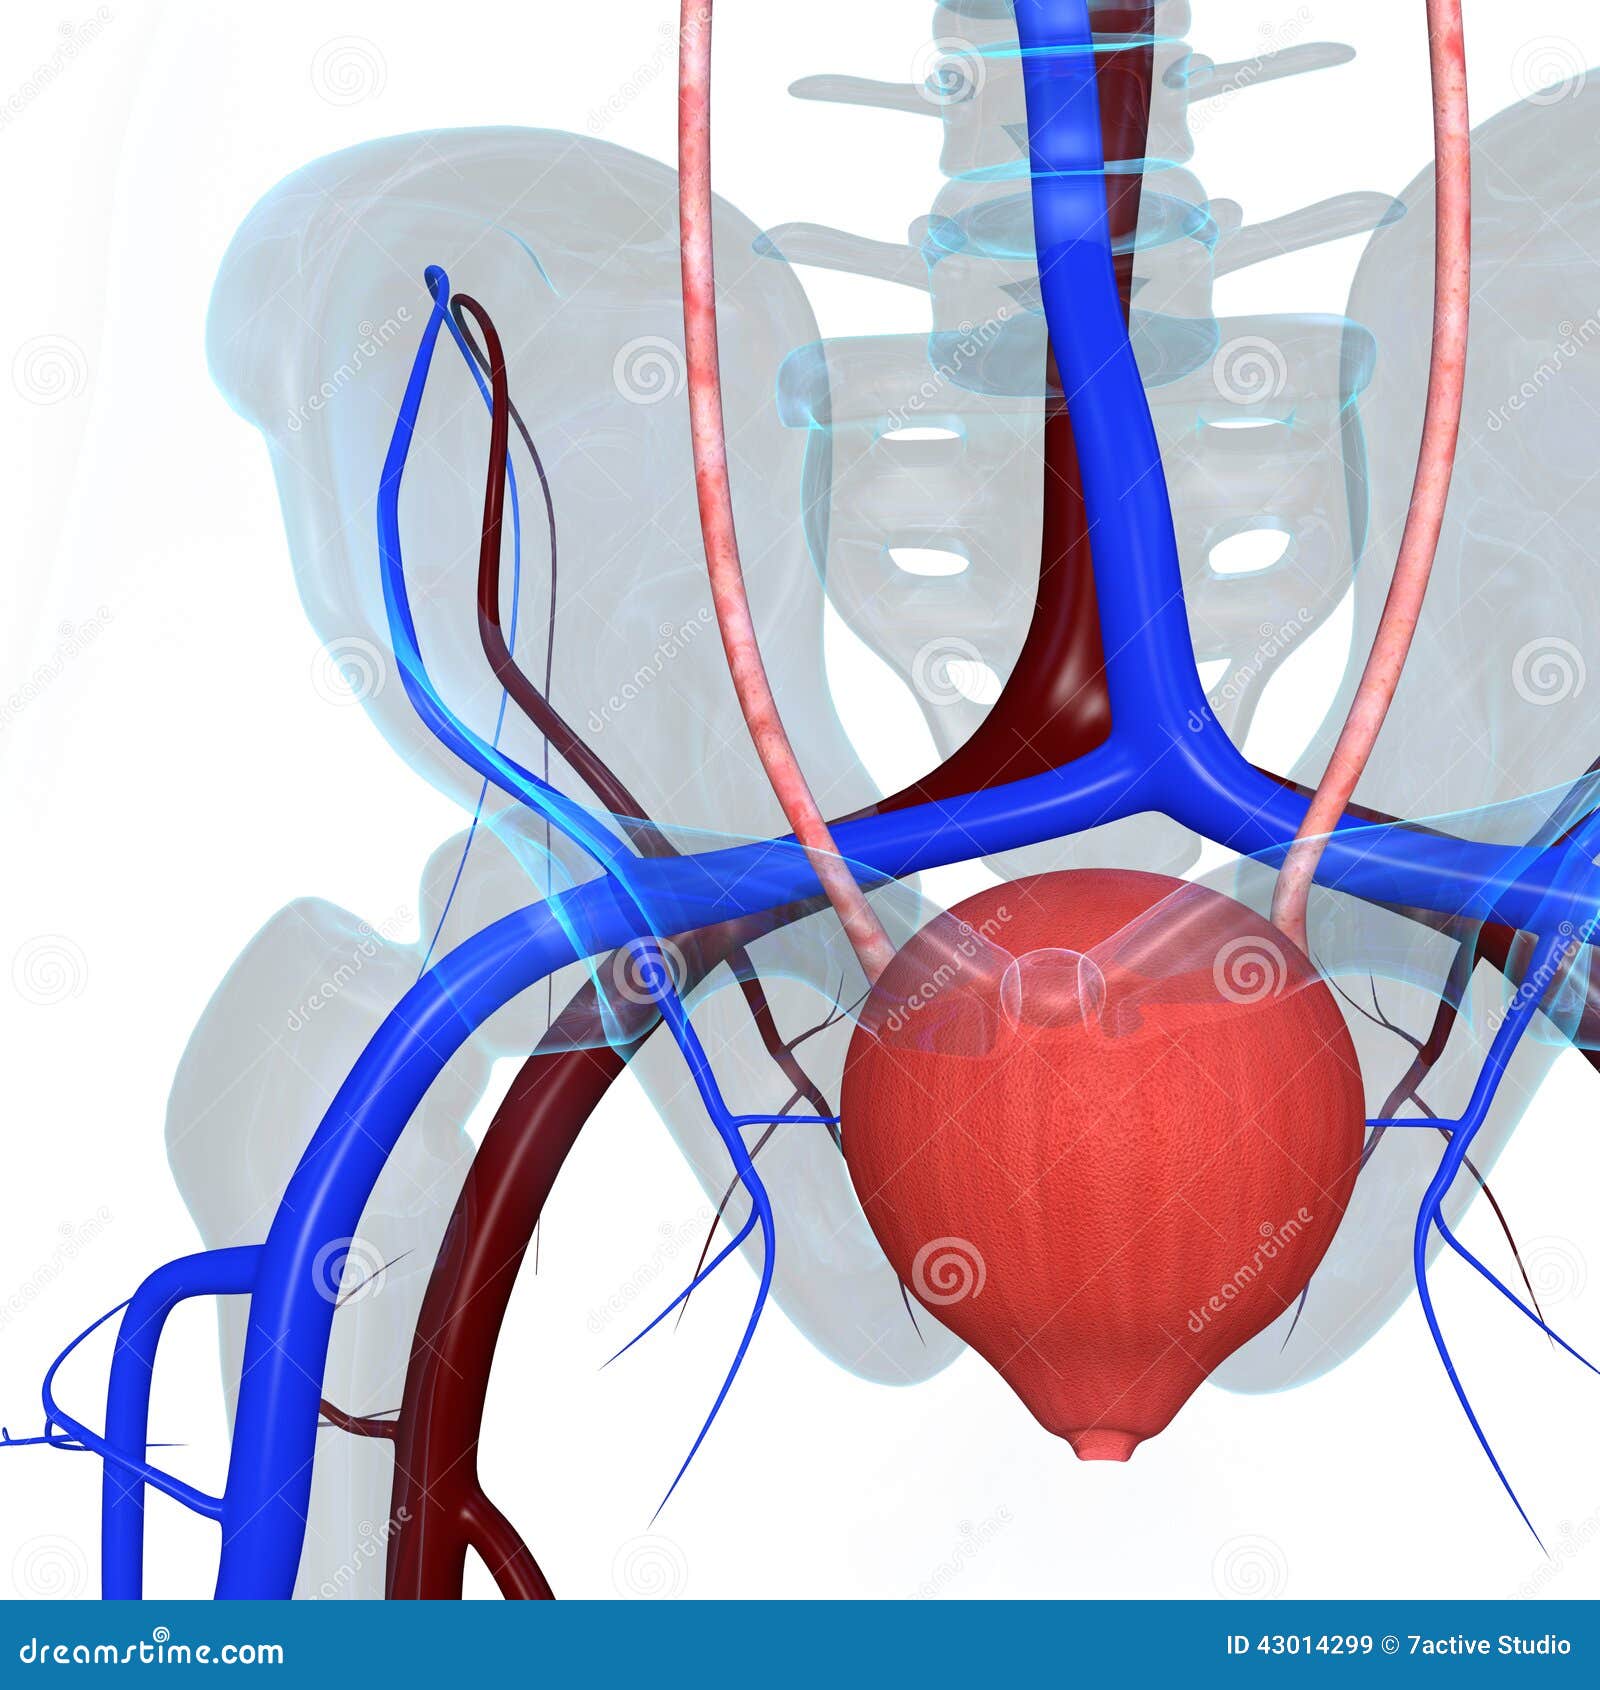

location of the bladder in the human body

Posts: location of the bladder in the human body